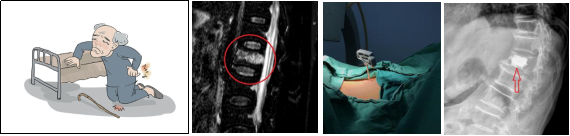

(三)、上頸椎高難度手術(shù)

寰樞椎又稱為上頸椎,是人體生命中樞的所在,該區(qū)域的手術(shù)難度大、風(fēng)險高,俗稱“手術(shù)禁區(qū)”。學(xué)科帶頭人王智運教授是國內(nèi)上頸椎領(lǐng)域的優(yōu)秀專家,在其帶領(lǐng)下,科室已成熟開展該技術(shù),所有手術(shù)患者均取得滿意臨床效果。